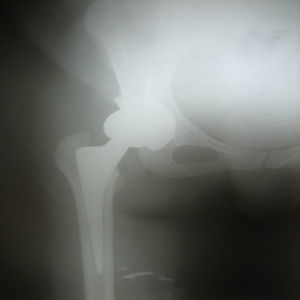

Arthriis of both hips pre op Arthriis of both hips post op Arthritis knee valgus deformity pre op Arthritis knee valgus deformity post op

coimbatore-orthopaedic-joint-replacement-maternity-child-welfare-centre-india Uncemented Hip Replacement

NEW TECHNIQUE FOR HIP ARTHRITIS

30 years old lady presented with complaint of pain right hip since 7 yrs and getting worse since 1 month. She is unable to walk and stand for a long time.

On examination she is having a painful limp, shortening of right lower limb, her hip movements are restricted and painful.

Xray showed evidence of old perthes disease and secondary osteoarthritis of right hip.

Hip Arthritis

In view of her young age , an uncemented Total Hip Replacement was carried out.

Hip Arthritis Uncemented Replacement

Post operative period was uneventful and she is walking painfree from 2nd post operative day .